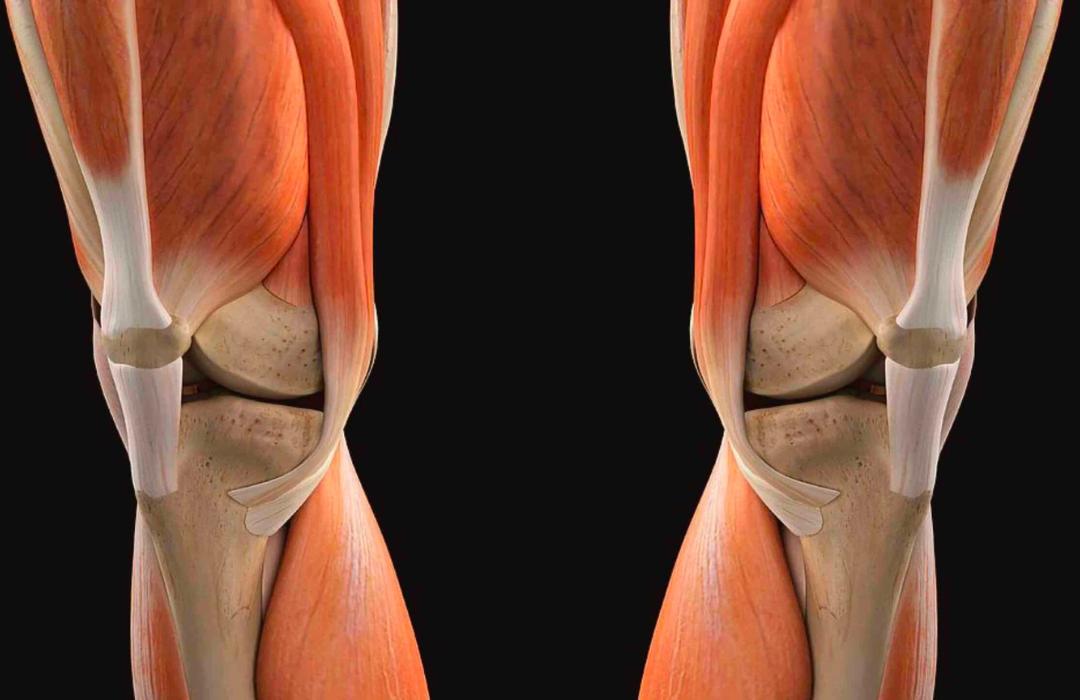

O realinhamento do mecanismo extensor é um procedimento cirúrgico que corrige alterações na trajetória da patela durante o movimento do joelho.

Quando a patela “sai do trilho”, desliza de maneira inadequada ou sofre luxações recorrentes, ocorre dor, instabilidade e desgaste acelerado da cartilagem.

O tratamento consiste em ajustar estruturas ósseas e/ou ligamentares para centralizar o movimento da patela, proporcionando maior estabilidade e redução da dor.

É o conjunto formado pelo quadríceps, tendão quadricipital, patela, tendão patelar e tuberosidade tibial. Ele é responsável por estender o joelho e estabilizar a patela durante o movimento.